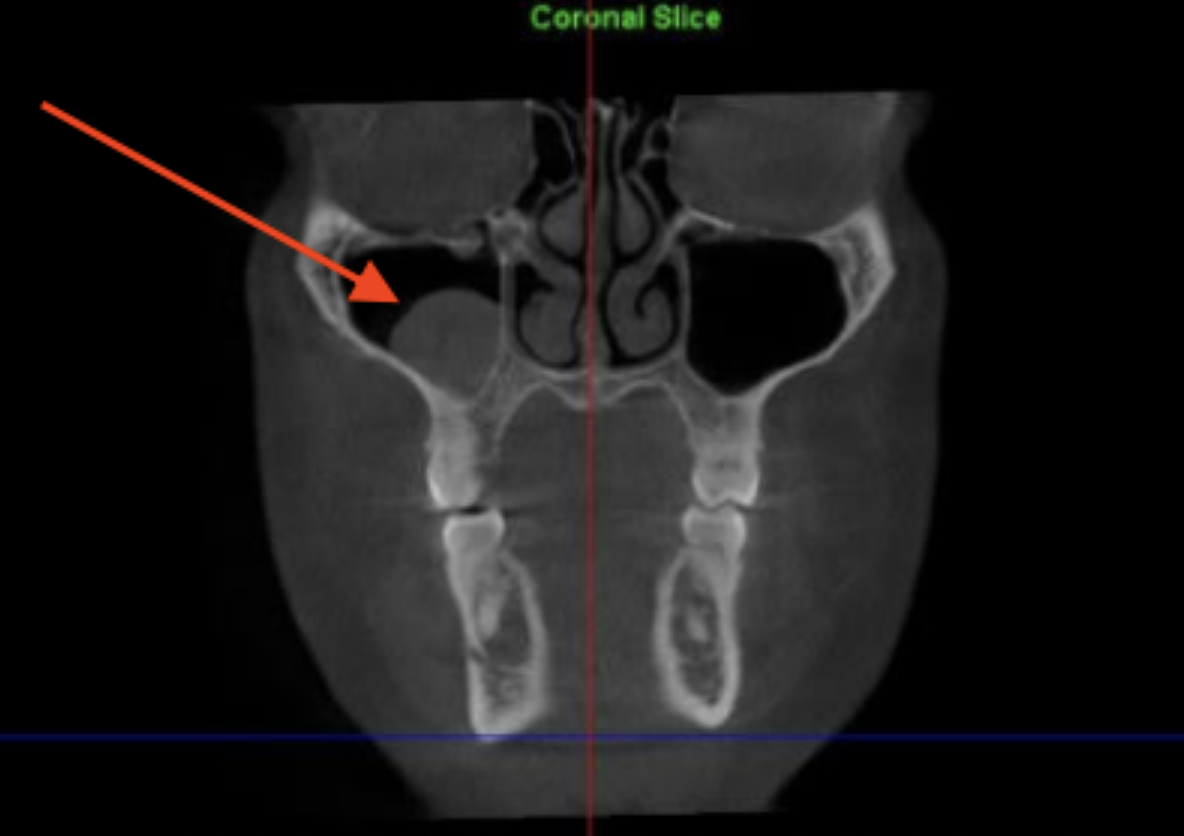

Sinus mucous retention cyst Radiology Case Radiopaedia

Product Name: Maxillary sinus retention cyst saleParanasal sinuses retention cysts Radiology Reference Article Radiopaedia sale, PDF Maxillary Sinus Retention Cysts Protruding Into the Inferior Meatus Semantic Scholar sale, Optimal timing of endoscopic sinus surgery for the retention cyst of maxillary sinus The Journal of Laryngology Otology Cambridge Core sale, What is a Maxillary Sinus Retention Cyst sale, Ruptured Maxillary Retention Cyst Cause of Unilateral Rhinorrhea after Trauma American Journal of Neuroradiology sale, Panoramic radiographs with images suggestive of a bilateral mucous. Download Scientific Diagram sale, Clinical and Experimental Otorhinolaryngology sale, Mucous retention cysts of maxillary sinus Radiology Case Radiopaedia sale, Ruptured Maxillary Retention Cyst Cause of Unilateral Rhinorrhea after Trauma American Journal of Neuroradiology sale, Unusually large radicular cyst presenting in the maxillary sinus BMJ Case Reports sale, Sphenoid Sinus Mucous Retention Cyst vs. Mucocele correction Slide 5 sale, Maxillary sinus mucous retention cyst removal thoughts sale, Are mucous retention cysts and pseudocysts in the maxillary sinus a risk factor for dental implants A systematic review. Abstract Europe PMC sale, What does left maxillary sinus small retention cyst noted mean in radiology Quora sale, Paranasal sinuses retention cysts Radiology Reference Article Radiopaedia sale, Combined vascular malformation and retention cyst in the maxillary sinus ScienceDirect sale, Optimal timing of endoscopic sinus surgery for the retention cyst of maxillary sinus The Journal of Laryngology Otology Cambridge Core sale, Mucucoele of the maxillary sinus and the eye Eye sale, Endoscopic sinus surgery for maxillary sinus mucoceles Head Face Medicine Full Text sale, Surgical outcomes between two endoscopic approaches for maxillary cysts ScienceDirect sale, 330KB 2001 null null null null 3 3 2003 null 5wIhQ6 k1nu nM sale, Clear Lake Medical Center ENT Mucous retention cysts develop in the lining sinuses. Unless they block drainage of your sinuses these cysts typically do not cause pain infection or breathing issues sale, Frequency and characteristics of retention cysts in the maxillary sinus in a Turkish patient population international journal of stomatology occlusion medicine sale, Sleep Apnea Sleep and Brain sale, Sinus mucous retention cyst Radiology Case Radiopaedia sale, Endoscopic sinus surgery for maxillary sinus mucoceles Head Face Medicine Full Text sale, Automatic diagnosis of retention pseudocyst in the maxillary sinus on panoramic radiographs using a convolutional neural network algorithm Scientific Reports sale, Imaging in Sinonasal Disorders IntechOpen sale, Mucous retention pseudocyst MRP of the right maxillary sinus on. Download Scientific Diagram sale, Severe facial pain and removal of maxillary sinus mucous retention cyst BMJ Case Reports sale, Maxillary Sinus Mucocele sale, Association between the seasonal changes and mucous retention cyst of maxillary antrum in cone beam computed tomography images in a sample population of Isfahan Iran Semantic Scholar sale, Symptomatic mucous retention cysts of the maxillary sinus case report sale, Clinical evaluation of sinus bone graft in patients with mucous retention cyst Maxillofacial Plastic and Reconstructive Surgery Full Text sale, Clinical evaluation of sinus bone graft in patients with mucous retention cyst Maxillofacial Plastic and Reconstructive Surgery Full Text sale.